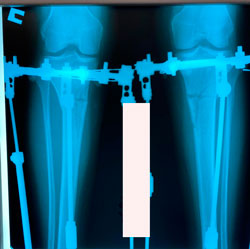

рентген перед фиксацией

Вложения